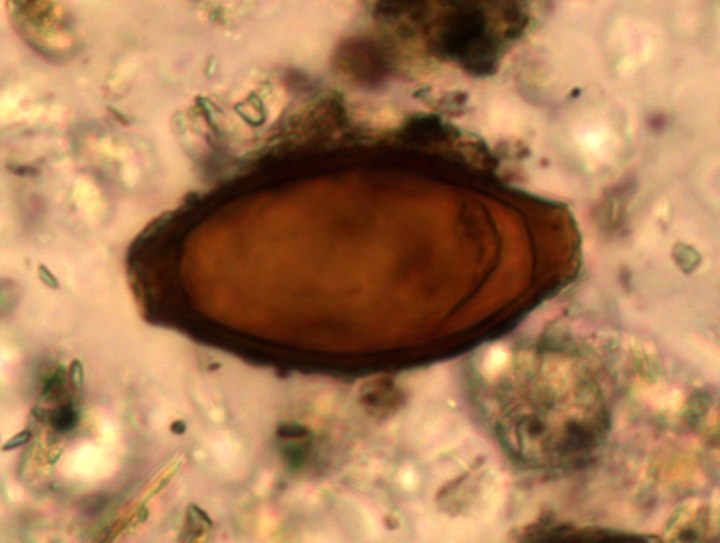

Tuttavia, una nuova ricerca inglese ha rivelato che, nonostante tutte queste innovazioni, parassiti intestinali come vermi a frusta, vermi cilindrici e Entamoeba histolytica, non diminuirono come previsto rispetto alla precedente Età del Ferro, ma addirittura aumentarono.

Non solo alcuni parassiti intestinali sembrano aumentare con l’arrivo dei Romani, ma Mitchell avrebbe anche scoperto che, nonostante i loro bagni regolari, gli ectoparassiti come pidocchi e pulci erano diffusi tanto fra i Romani quanto fra i Vichinghi e nelle popolazioni medievali, quando i bagni non erano molto diffusi. «La ricerca moderna ha mostrato che i bagni, l’acqua potabile pulita e la rimozione delle feci dalle strade diminuiscono il rischio di malattie infettive e parassiti», ha detto Mitchell. «Dunque dovremmo aspettarci un decremento dei parassiti come i vermi a frusta e i vermi cilindrici – invece ne troviamo un aumento. La domanda è: perché?».

Un’altra possibile spiegazione sarebbe l’uso romano di impiegare gli escrementi umani come fertilizzante nei campi. Sebbene la ricerca moderna abbia dimostrato che questo aumenta i raccolti, esso può anche diffondere le uova di parassiti che poi possono sopravvivere nelle piante. «È possibile che le leggi sui servizi igienici per rimuovere le feci dalle strade portassero in realtà a infettare la popolazione, dato che poi venivano spesso usate per fertilizzare i campi agricoli intorno alle città», spiega il ricercatore inglese.

Lo studio ha scoperto che le uova di botriocefalo (un verme piatto che si sviluppa nei pesci) erano sorprendentemente diffuse nel periodo romano rispetto all’Età del Bronzo e del Ferro in Europa. Mitchell crede che la causa di ciò sia nientemeno che la salsa preferita dai Romani, il garum.